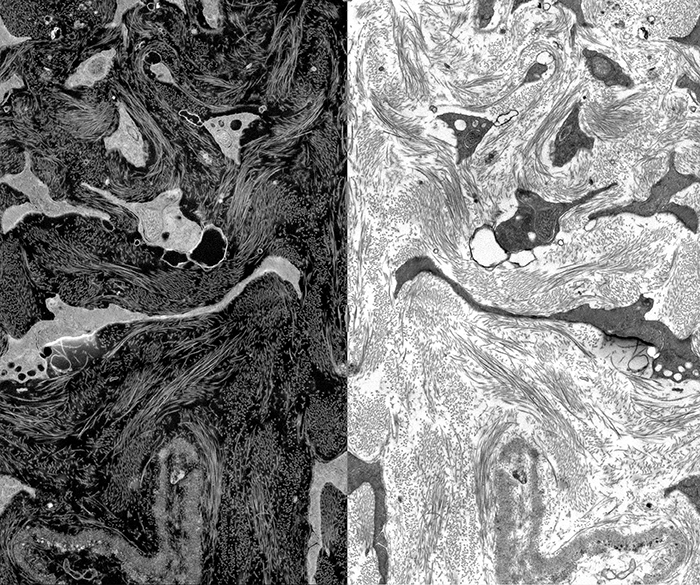

Diseased Retina